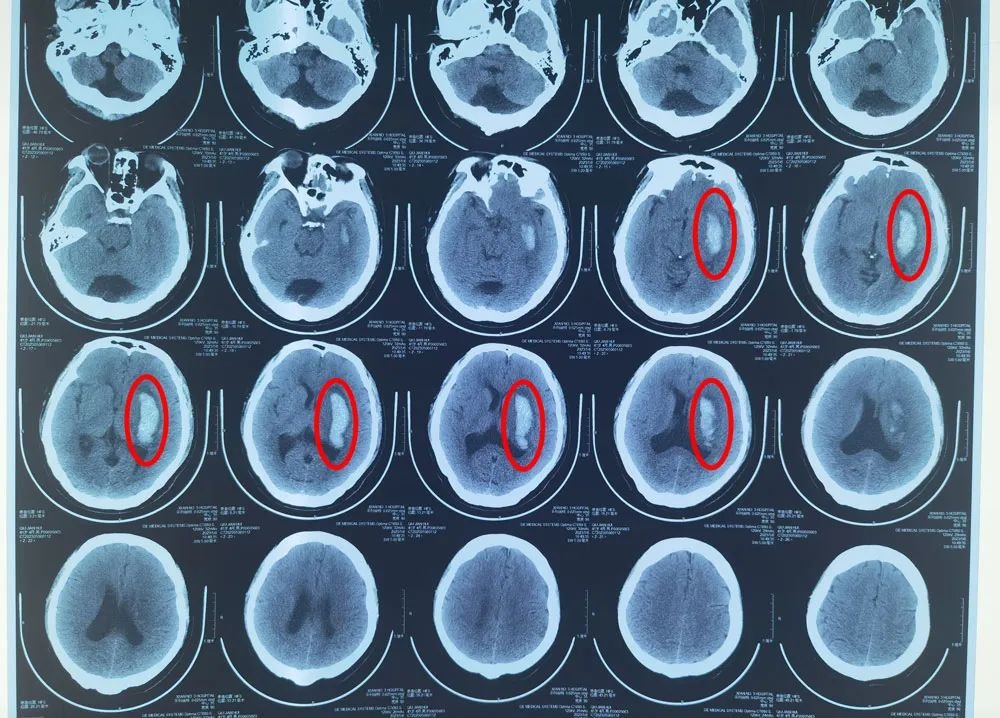

▲抽出血肿24ml

41岁的高先生因突发右侧肢体活动障碍伴言语不能被送入西安市第三医院急诊科,患者行头颅CT提示左侧基底节区脑出血,形成血肿,如不进行手术治疗,很可能会留下终身残疾的后遗症,对日后的生活质量造成很大的影响。但由于担心手术风险,患者家属迟迟犹豫不决。传统的穿刺手术是通过CT定位后,再通过测量病灶位置,确定入颅点,穿刺过程中医生无法直观地看到患者大脑皮层的血管、脑回等,稍不留意就有可能损伤正常的脑组织、重要的神经功能,存在置管不精准、手术风险大的弊端。

术后,影像检查显示,高先生的脑部血肿几乎完全消失,肢体功能也有明显改善。

▲手术前

▲手术后